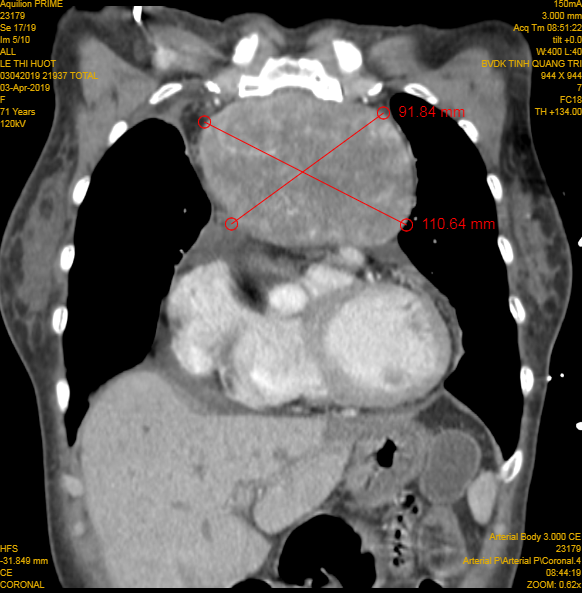

“Kíp mổ của Khoa Ung bướu đã tiến hành mở ngực đường giữa, cắt xương ức, tiếp cận khối u, cô lập các mạch máu nuôi u, bóc tách khối u có kích thước 12 x10 cm, nặng khoảng 1 kg ra khỏi thành ngực thành công sau 3 giờ phẫu thuật”, BS Dũng nói.

Hình ảnh khối u lớn được chụp lại. Ảnh: BVĐKQT.